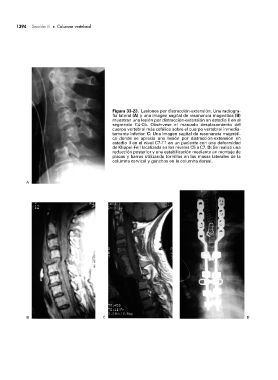

Figura 33-23. Lesiones por distracción-extensión. Una radiogra-

fía lateral (A) y una imagen sagital de resonancia magnética (B)

muestran una lesión por distracción-extensión en estadio II en el

segmento C4-C5. Obsérvese el marcado desplazamiento del

cuerpo vertebral más cefálico sobre el cuerpo vertebral inmedia-

tamente inferior. C: Una imagen sagital de resonancia magnéti-

ca donde se aprecia una lesión por distracción-extensión en

estadio II en el nivel C7-T1 en un paciente con una deformidad

de Klippel-Feil localizada en los niveles C5 a C7. D: Se realizó una

reducción posterior y una estabilización mediante un montaje de

placas y barras utilizando tornillos en las masas laterales de la

columna cervical y ganchos en la columna dorsal.